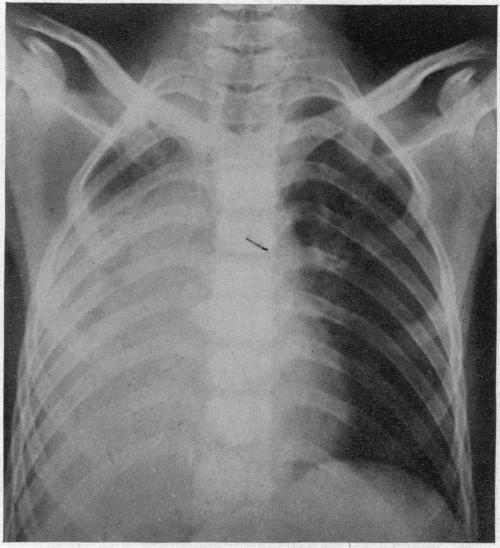

ACUTE MASSIVE COLLAPSE OF THE LUNGS: A DISCUSSION OF ITS MECHANISM AND OF ITS RELATION TO FOREIGN BODIES IN THE BRONCHI AND POST-OPERATIVE COMPLICATIONS.

Ann Surg. 1925 Sep;82(3):364-89. doi: 10.1097/00000658-192509010-00005.